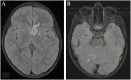

A 7-year-old child of Turkish origin presented with headache and vomiting in the context of prolonged fever of unknown source. At examination, oral candidiasis and chronic onychomycosis were noted. A Candida meningoencephalitis was diagnosed and intravenous Amphotericin B liposomal was given during 6 months relayed by oral Fluconazole after regression of CNS lesions was observed on MRI. A complete immune evaluation was performed, and genetic analysis detected homozygous CARD9 mutation. CARD9 deficiency have been associated with invasive candidiasis in otherwise healthy patients. Culture of the cerebrospinal fluid grew for multisensitive Candida albicans. Brain magnetic resonance (MRI) showed the presence of focal lesions in the left caudate nucleus and in the right cerebellar hemisphere. Medullar MRI showed diffuse meningeal nodular lesions. Treatment with intravenous amphotericin B liposomal was given during 6 months relayed by oral fluconazole after regression of CNS lesions was observed on MRI. A complete immune evaluation was performed and genetic analysis detected a homozygous CARD9 mutation. CARD9 deficiency have been associated with invasive candidiasis in otherwise healthy patients.